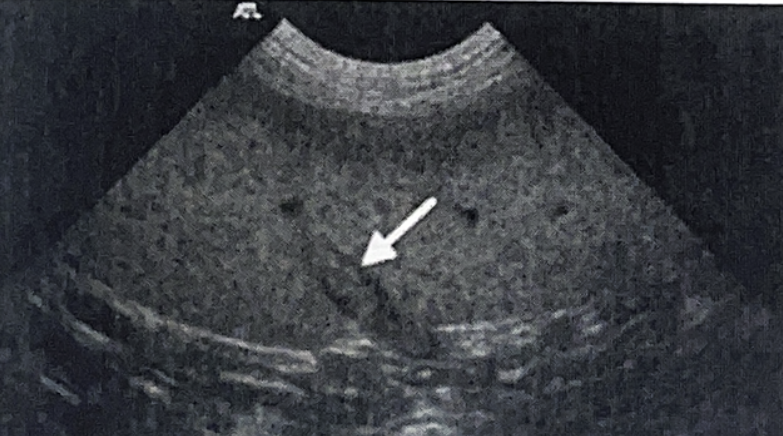

초음파 소견

- Hepatosplenomegaly, honey-comb appearance 나타남. (honeycomb=lymphoma는 아님)

- Focal한 mass가 생길 수 있음.